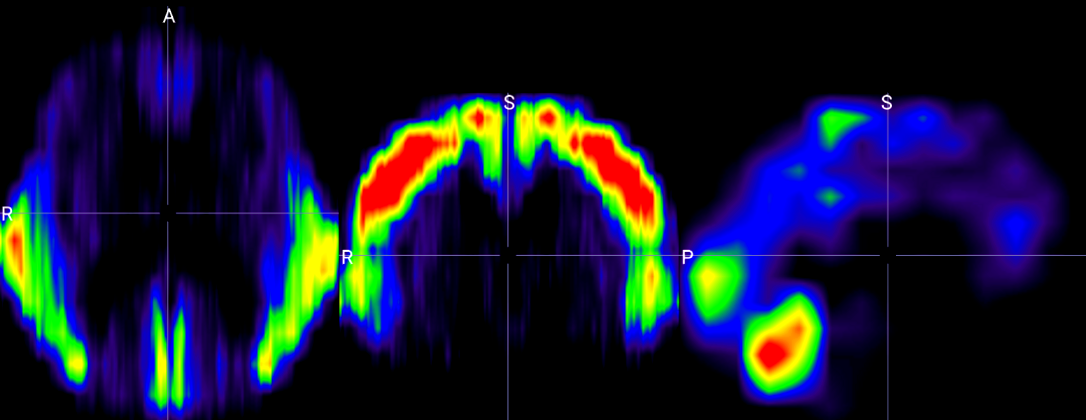

To further interpret the spatial focus of the Vision Transformer within the proposed BrainRotViT framework, we visualize the mean attention distribution across subjects in the validation set. Figure 4(a) illustrates the aggregated attention heatmap derived from the middle sagittal slice (slice index 80) averaged over all n=1022n=1022 validation samples. The 3D attention visualization in Figure 4(b) reveals several neuroanatomical regions exhibiting strong activation from the model, corresponding to areas known to undergo age-related structural and functional changes.

Figure 4: Model Interpretation. (a): Example of per-slice attention map extracted from vision transformer. (b) Mid-slice section views of fused 3D attention map along axial, coronal, and sagittal planes (from left to right).(c): Saliency map of trained residual CNN extracted through guided back propagation. (d)–(k): 3D attention map previews by age range.